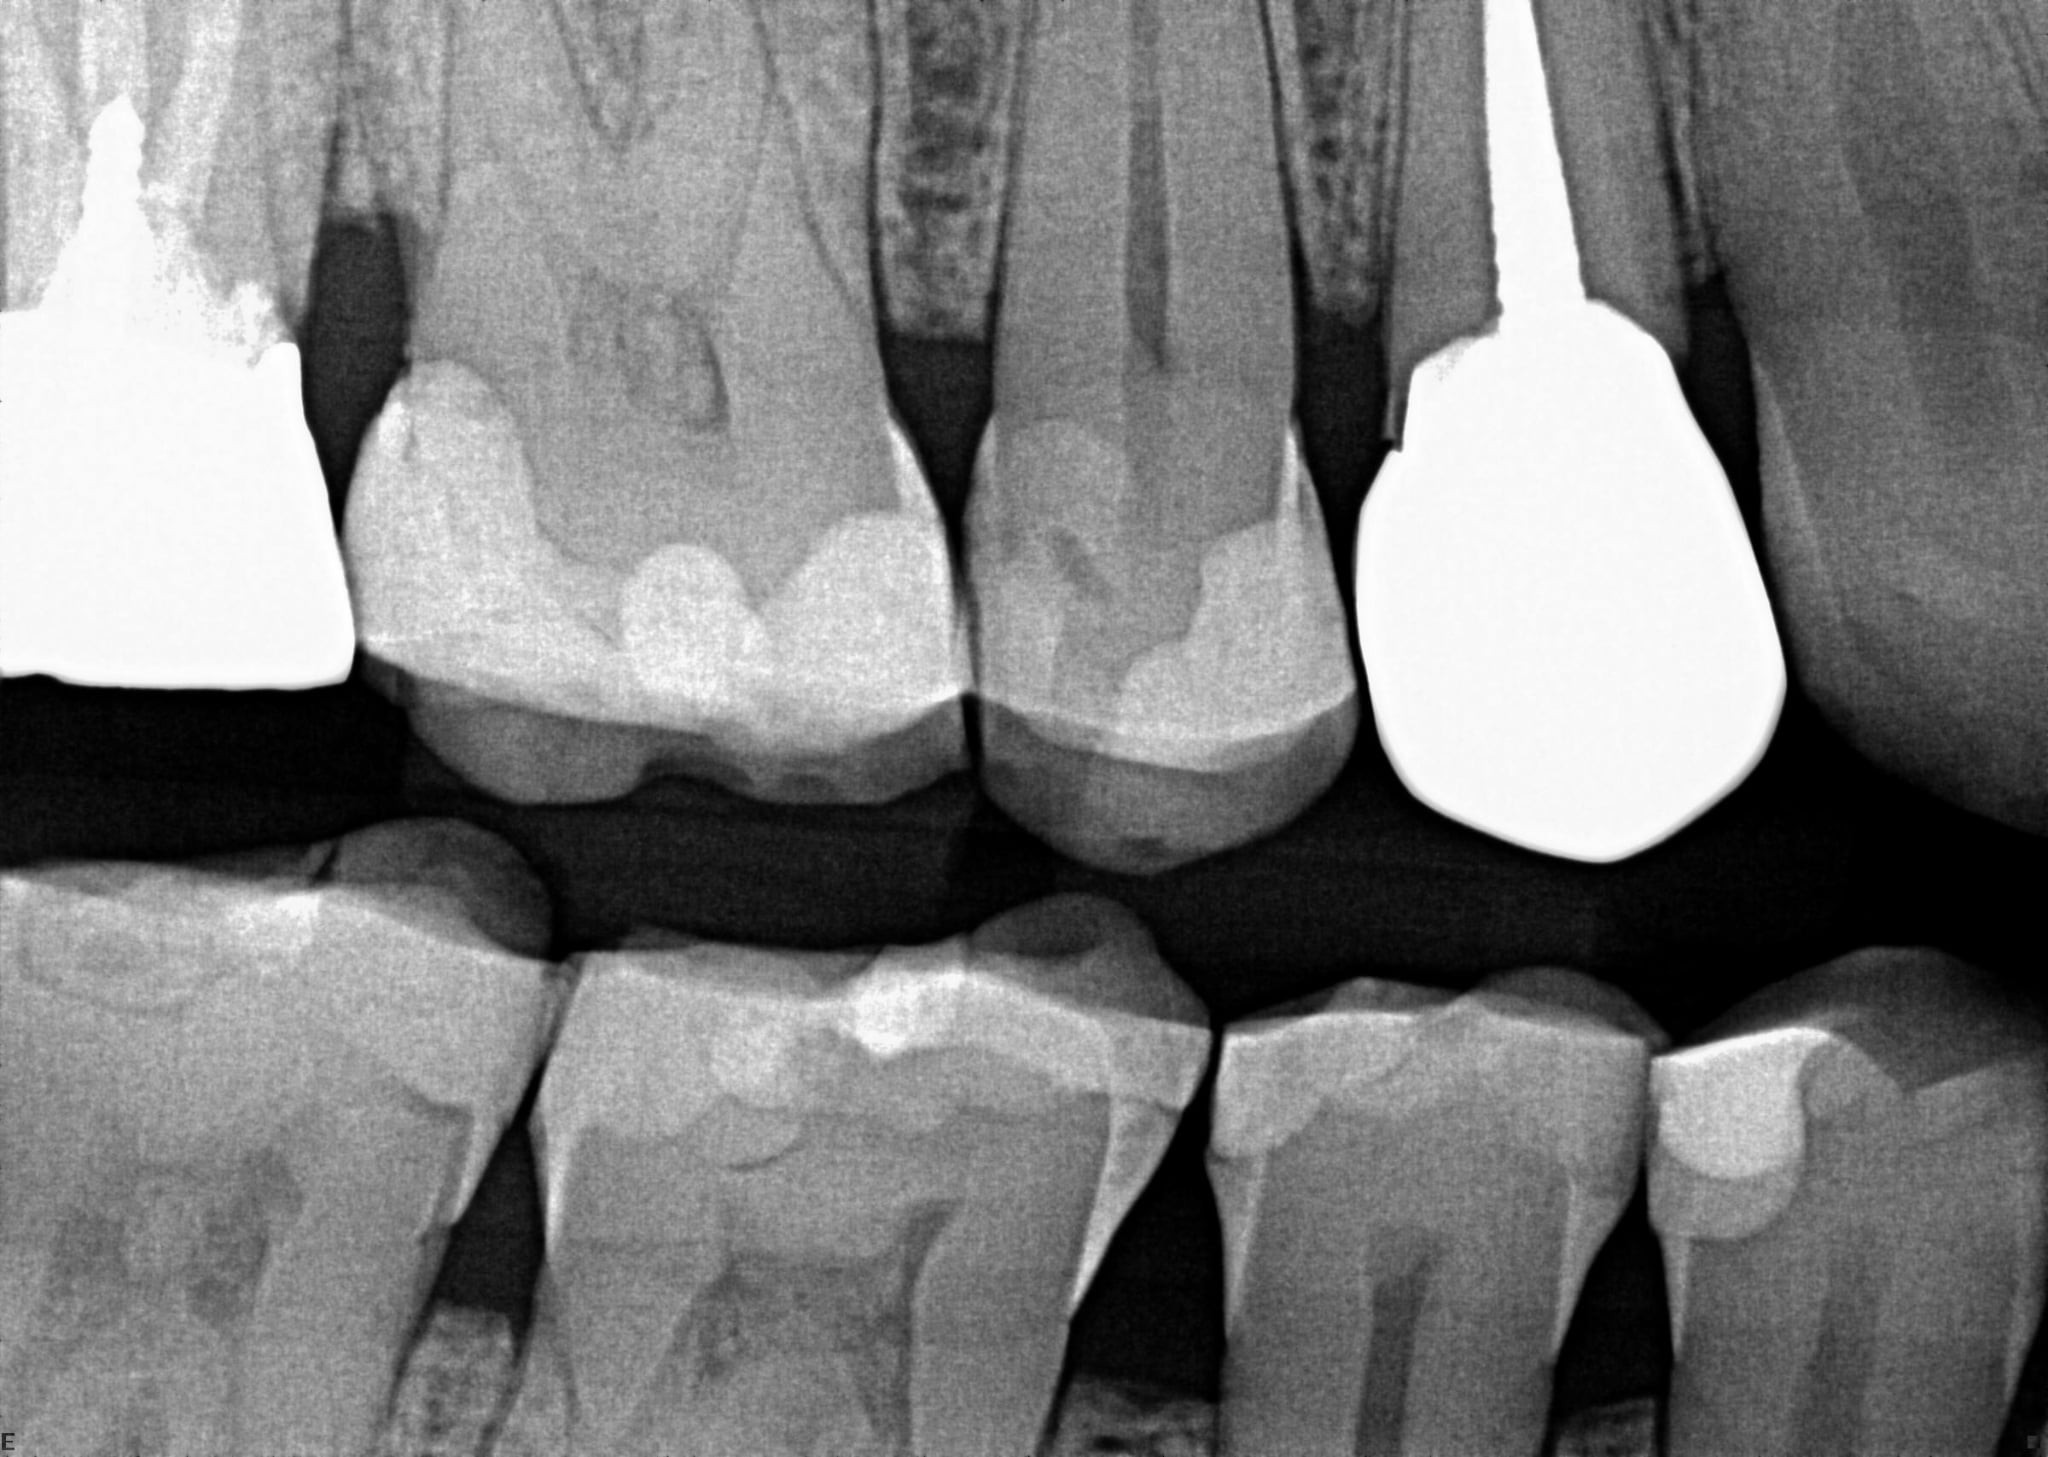

1. On which surface a recurrent caries can be detected?

2. On which surface a recurrent caries can be detected?

None of the teeth shows recurrent caries